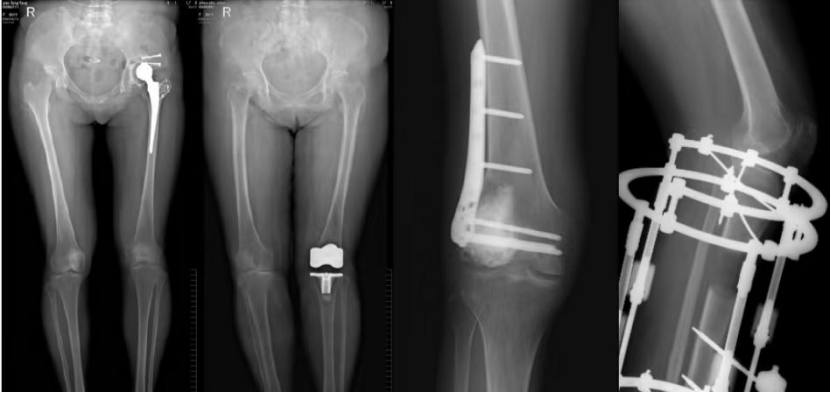

2.应用适应症:全下肢摄影—人工髋关节、膝关节置换以及下肢不等长畸形的矫正和O、X型腿畸形的矫正。可进行骨密度检查和负重全下肢扫描。

股骨颈骨质量术前评估联合股骨、膝关节置换等术后评价